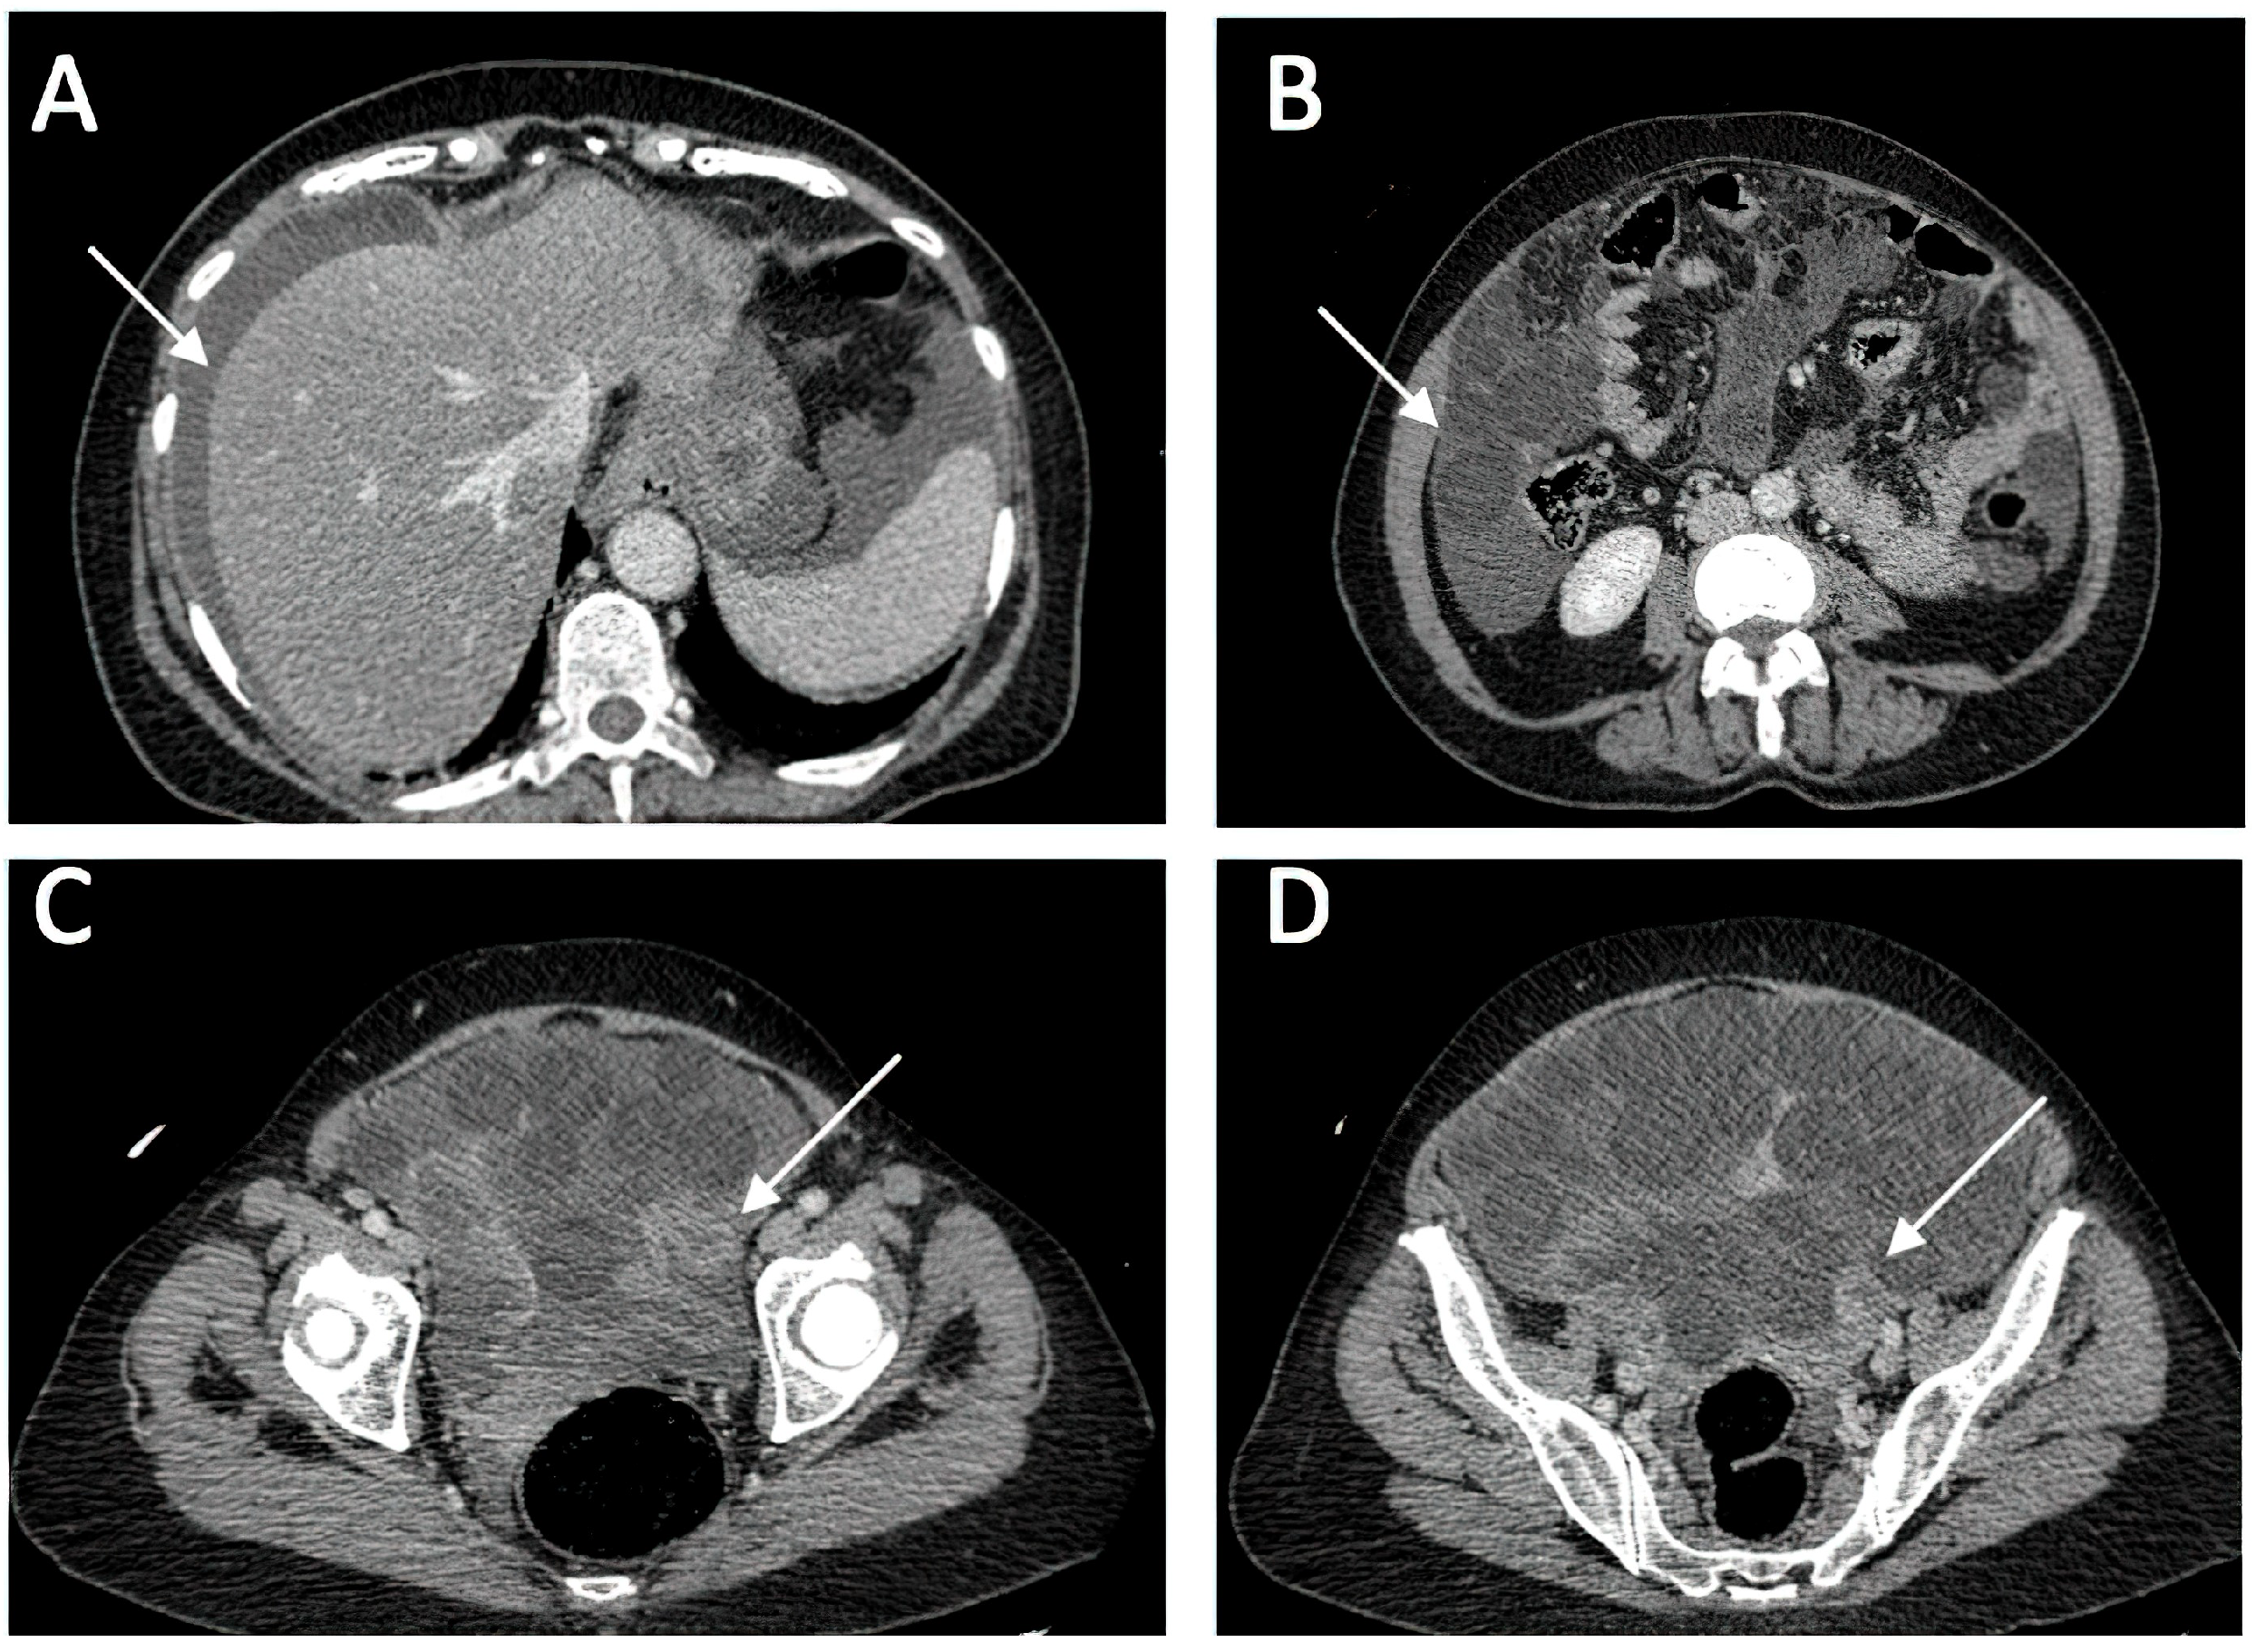

Ruptured Ovarian Cystic Teratoma: A Rare Diagnosis, Easily to Be Confused with Peritoneal Carcinomatosis

3. Case Presentation